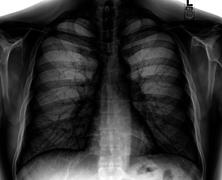

Different views (also known as projections) of the chest can be obtained by changing the relative orientation of the body and the direction of the x-ray beam. The most common views are posteroanterior, anteroposterior, and lateral. In a posteroanterior (PA) view, the x-ray source is positioned so that the x-ray beam enters through the posterior (back) aspect of the chest and exits out of the anterior (front) aspect, where the beam is detected. To obtain this view, the patient stands facing a flat surface behind which is an x-ray detector. A radiation source is positioned behind the patient at a standard distance (most often 6 feet, 1,8m), and the x-ray beam is fired toward the patient.

In anteroposterior (AP) views, the positions of the x-ray source and detector are reversed: the x-ray beam enters through the anterior aspect and exits through the posterior aspect of the chest. AP chest x-rays are harder to read than PA x-rays and are therefore generally reserved for situations where it is difficult for the patient to get an ordinary chest x-ray, such as when the patient is bedridden. In this situation, mobile X-ray equipment is used to obtain a lying down chest x-ray (known as a "supine film"). As a result, most supine films are also AP.

Lateral views of the chest are obtained in a similar fashion as the posteroanterior views, except in the lateral view, the patient stands with both arms raised and the left side of the chest pressed against a flat surface.

Typical views

Required projections can vary by country and hospital, although an erect posteroanterior (PA) projection is typically the first preference. If this is not possible, then an anteroposterior view will be taken. Further imaging depends on local protocols which is dependent on the hospital protocols, the availability of other imaging modalities and the preference of the image interpreter. In the UK, the standard chest radiography protocol is to take an erect posteroanterior view only and a lateral one only on request by a radiologist.[5] In the US, chest radiography includes a PA and Lateral with the patient standing or sitting up. Special projections include an AP in cases where the image needs to be obtained stat and with a portable device, particularly when a patient cannot be safely positioned upright. Lateral decubitus may be used for visualization of air-fluid levels if an upright image cannot be obtained. Anteroposterior (AP) Axial Lordotic projects the clavicles above the lung fields, allowing better visualization of the apices (which is extremely useful when looking for evidence of primary tuberculosis).